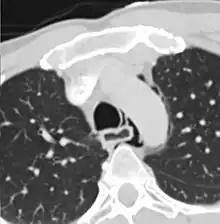

| Axial CT image through the upper chest showing extraluminal air (Pneumomediastinum) surrounding the trachea and esophagus | |

The diagnosis of Boerhaave syndrome is suggested on the plain chest radiography and confirmed by chest CT scan. The initial plain chest radiograph is almost always abnormal in patients with Boerhaave syndrome and usually reveals mediastinal or free peritoneal air as the initial radiologic manifestation. With cervical esophageal perforations, plain films of the neck show air in the soft tissues of the prevertebral space.

Hours to days later, pleural effusion(s) with or without pneumothorax, widened mediastinum, and subcutaneous emphysema is typically seen. CT scan may show esophageal wall edema and thickening, extraesophageal air, periesophageal fluid with or without gas bubbles, mediastinal widening, and air and fluid in the pleural spaces, retroperitoneum or lesser sac.